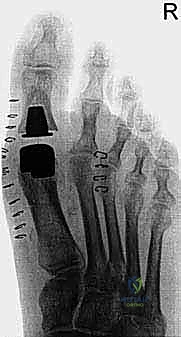

1. استئصال النتوءات العظمية الظهرية (Cheilectomy)

تُعد هذه العملية الخيار الذهبي للمرضى في المراحل المتوسطة (الدرجة 1، 2، وبداية 3) الذين لا يزال لديهم جزء من الغضروف السليم. مصطلح "Cheilectomy" يعني حرفياً "إزالة الشفة"، ويشير إلى إزالة النتوء العظمي (Bone Spur) الموجود أعلى المفصل والذي يعيق الحركة.

يقوم الدكتور هطيف بعمل شق جراحي دقيق أعلى المفصل، ثم يُزيل النتوءات العظمية بدقة متناهية، بالإضافة إلى إزالة حوالي 20-30% من الجزء العلوي لرأس عظمة المشط. هذا الإجراء "يفتح" المفصل ويوفر مساحة كافية لإصبع القدم للانثناء لأعلى بحرية، مما يزيل الألم فوراً.

- الاستئصال (The Cheilectomy): باستخدام أدوات دقيقة، يقوم الدكتور هطيف بإزالة النتوء العظمي الظهري (Bone Spur) ويستأصل حوالي الثلث العلوي من رأس عظمة المشط.

- التحرير والتنظيف: يتم تنظيف المفصل من أي شظايا عظمية أو غضروفية حرة (Loose bodies)، ويتم تحرير الأنسجة الأخمصية لضمان استعادة أكبر قدر ممكن من الحركة.

- الاختبار: يقوم الجراح بثني الإصبع يدوياً أثناء العملية للتأكد من زوال العائق العظمي وأن نطاق الحركة (Dorsiflexion) قد تحسن بشكل مرضي (يستهدف عادة 60 إلى 70 درجة من الانثناء).